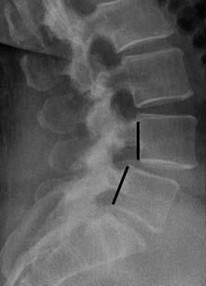

A) 椎體下陷:

| 當盤間盤承載力不足,無法承受上身的重量導致椎體下陷,壓迫神經。 |